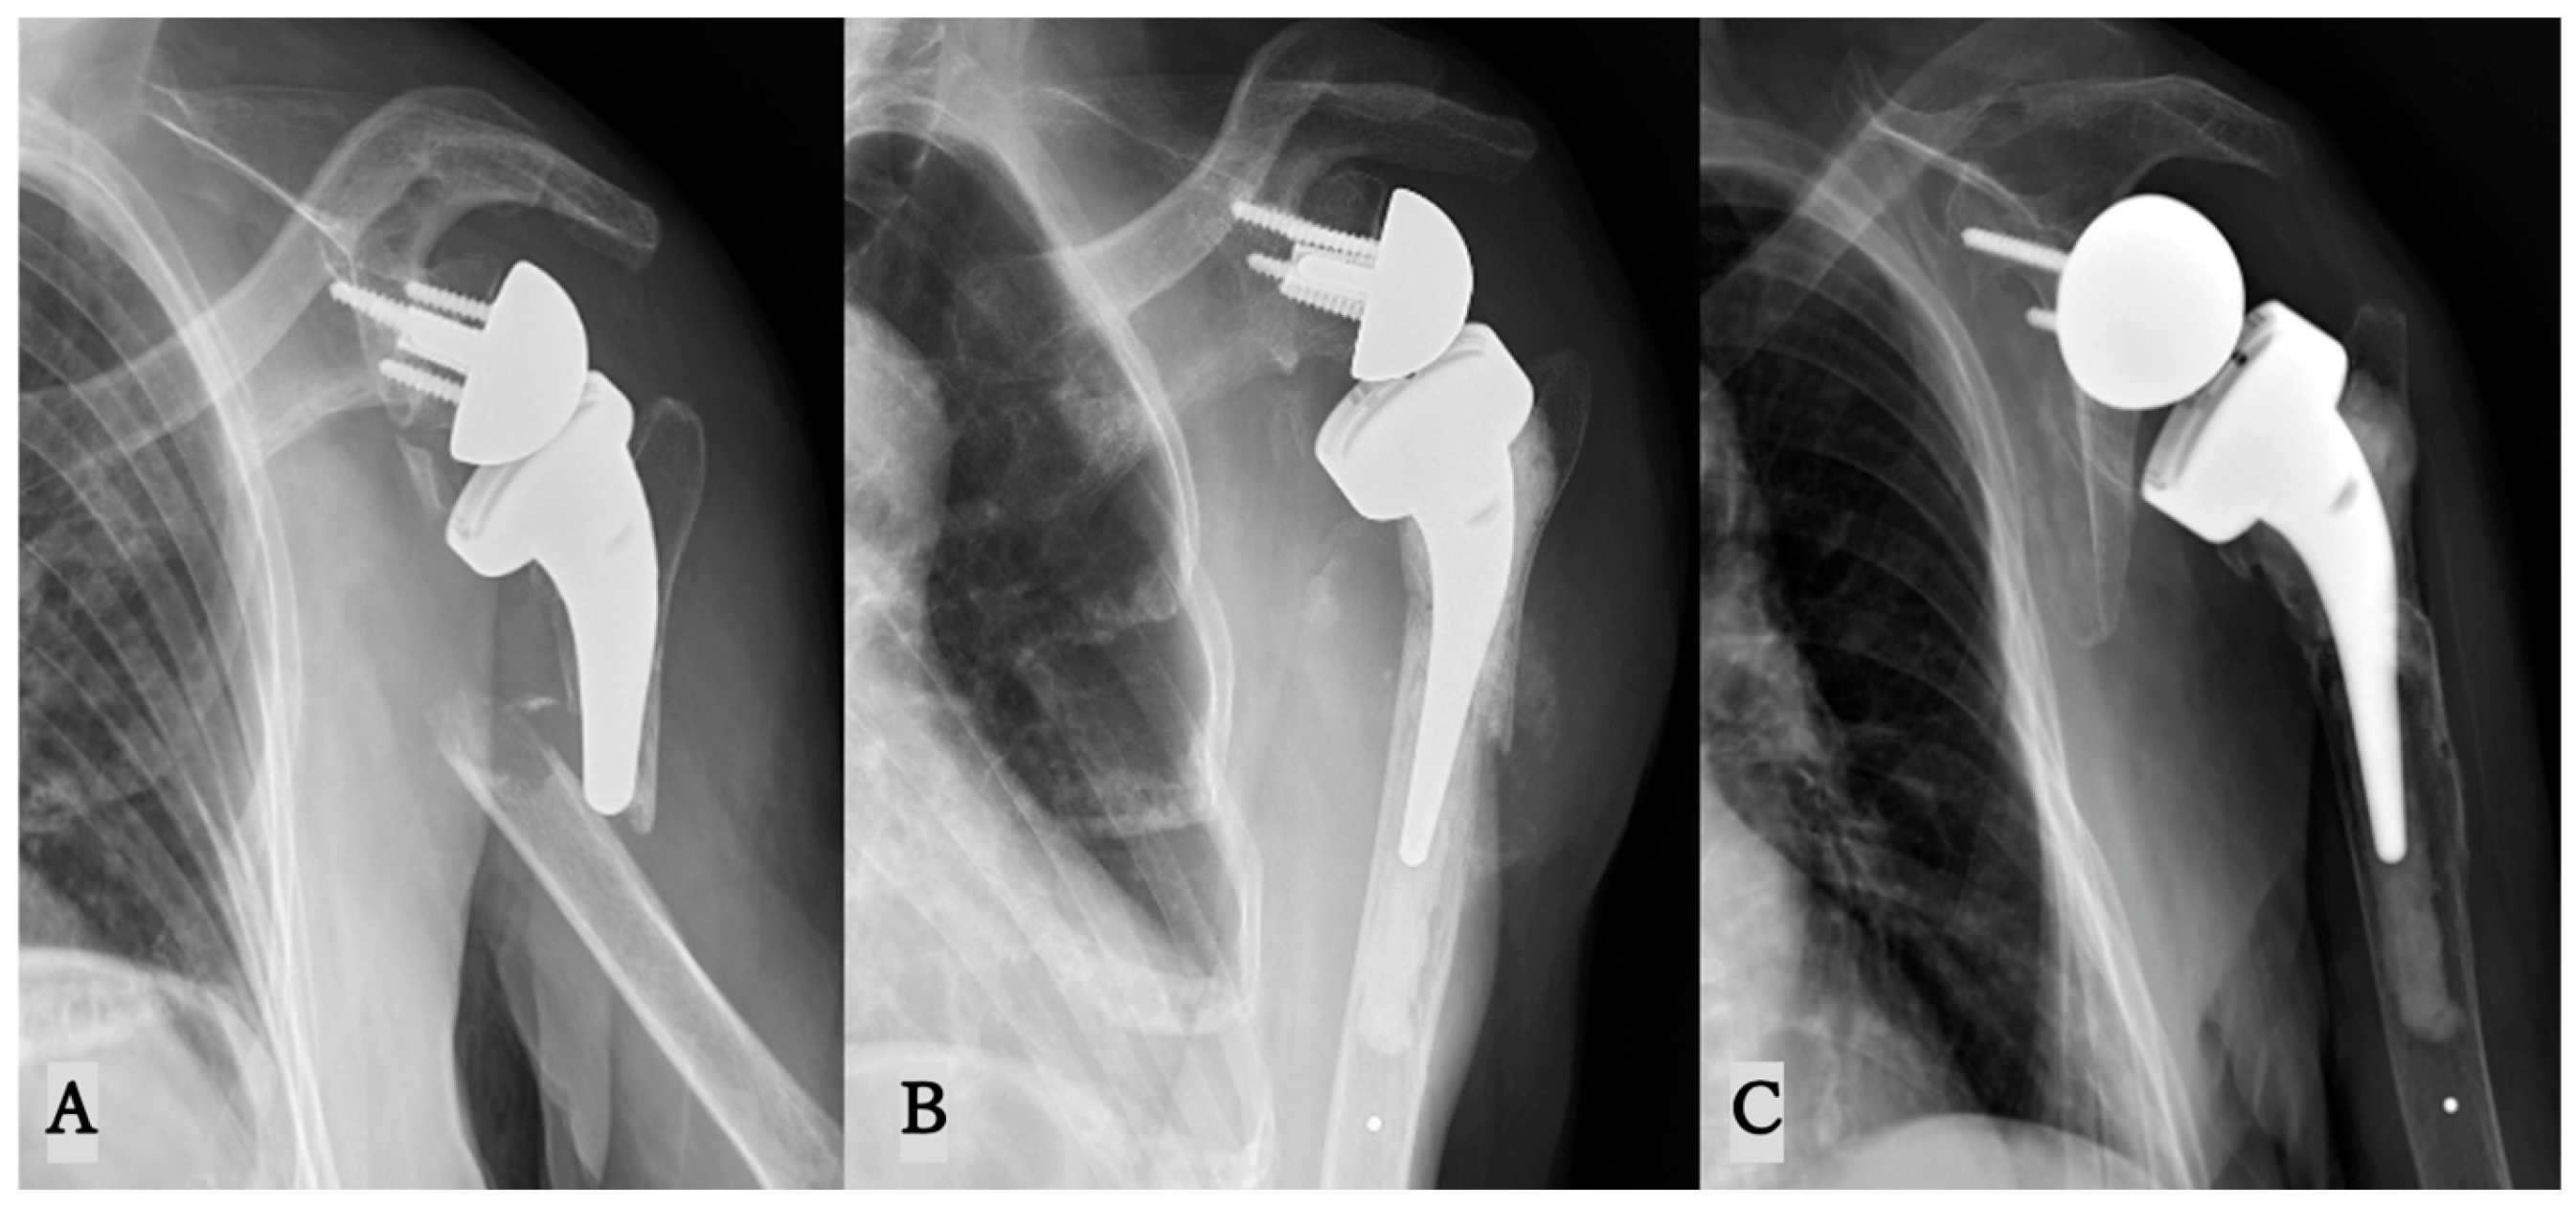

| Patient | Gender/Age | BMI (kg/m2) | Time from Primary RSA to Fracture (Days) | Stem of Primary RSA | Classification of PF by This Study |

|---|---|---|---|---|---|

| 1 | Female/80 | 25 | 469 | short/cementless | B3 |

| 2 | Female/74 | 27 | 1335 | short/cementless | B1 |

| 3 | Male/74 | 25 | 730 | short/cementless | B1 |

| 4 | Female/87 | 23 | 705 | short/cemented | B1 |

| 5 | Male/47 | 29 | 49 | short/cementless | B1 |